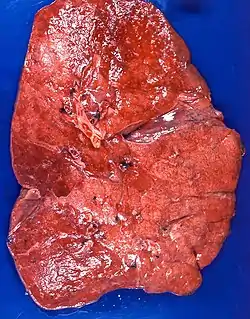

Lipid pneumonia, exogenous Case 108 | |

The gross appearance of a lipid pneumonia is that in which there is an ill-defined, pale yellow area on the lung. This yellow appearance explains the colloquial term "golden" pneumonia.[7]